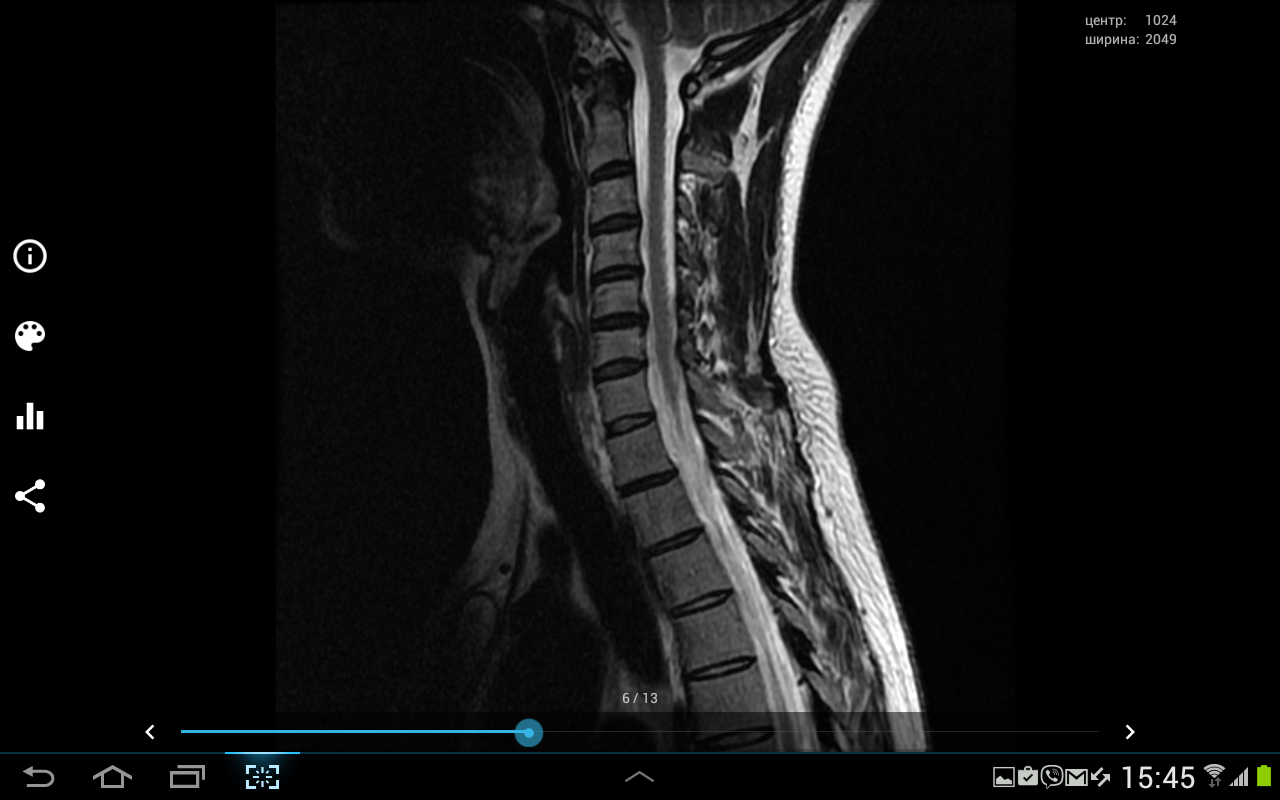

Здравствуйте подскажите пожалуйста надо делать операцию или нет? Наш нейрохирург говорит что надо, невролог говорит что не надо не знаю кого слушать, помогите. У меня ноющие боли в шее, переходящие на левую руку и под лопатку,иногда немеют кончики пальцев на руках, также есть иногда головные боли!?

- МРТ